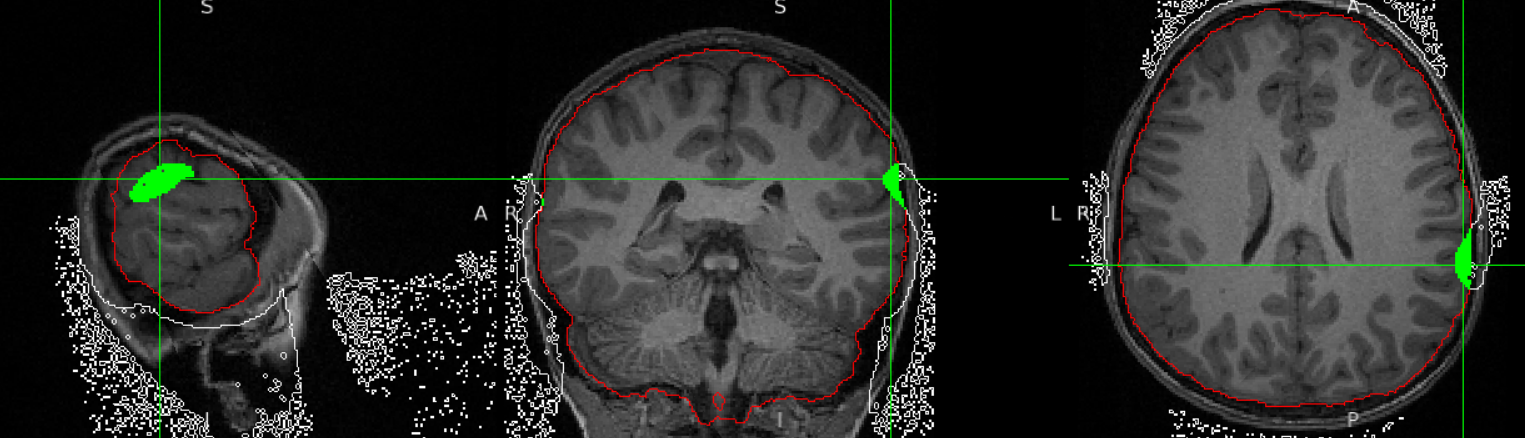

The attached picture shows a problem with the refacing ear mask clipping into the brain. In the screenshot, the grayscale image is the original MPRAGE (without refacing), the white outline is the difference between the original and _deFaced.nii (essentially where the refacing mask ends up), the red outline is a quick brainmask using Freesurfer's synthstrip, and the green is where the refacing mask and brainmask overlap.

This is just one example, but with this particular population, it happens roughly 10% of the time, with varying degree of severity. I'm wondering if this is because the population is kids, and so the distance between the surface of their brain and skin is a lot of times less than 10 1mm voxels, and maybe the ear mask was generated with adults? I also wonder if wearing the standard Siemens headphones, which are maybe even compressing what little tissue is there even a few more voxels is making the problem even a little worse.